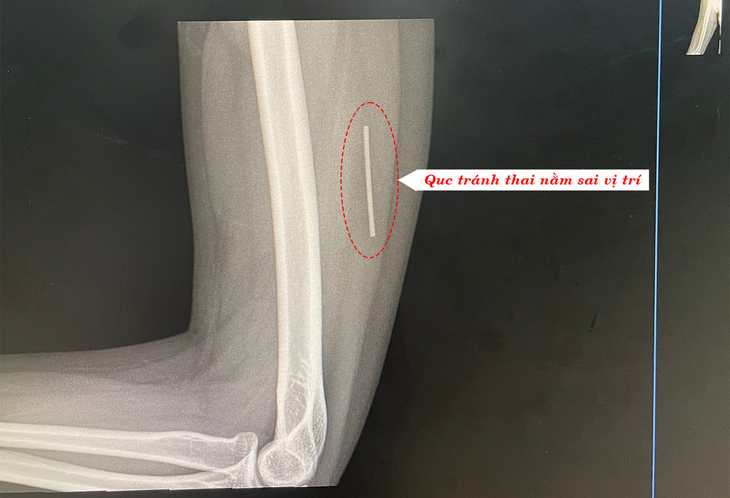

Hình ảnh chụp X-quang que tránh thai đi lạc vào sâu trong cơ bắp tay bệnh nhân – Ảnh: BVCC

Kết quả chụp X-quang cho thấy que tránh thai không nằm dưới da mà đã “đi lạc” sâu trong cơ bắp tay phải của bệnh nhân, dẫn đến tình trạng đau mỗi lần cử động.